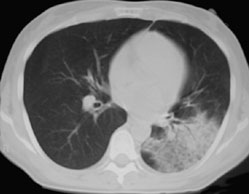

SIGNO DE LAS ALAS DE MARIPOSA INVERTIDAS

La presencia de infiltrados alveolares de disposición periférica y bilateral, respetando las regiones perihiliares, provoca una imagen opuesta a la del signo de las alas de mariposa. Este hallazgo se ve en la neumonía eosinófica.

La imagen de la TC muestra los focos de condensación alveolar periféricos y bilaterales, con predominio en el pulmón derecho.